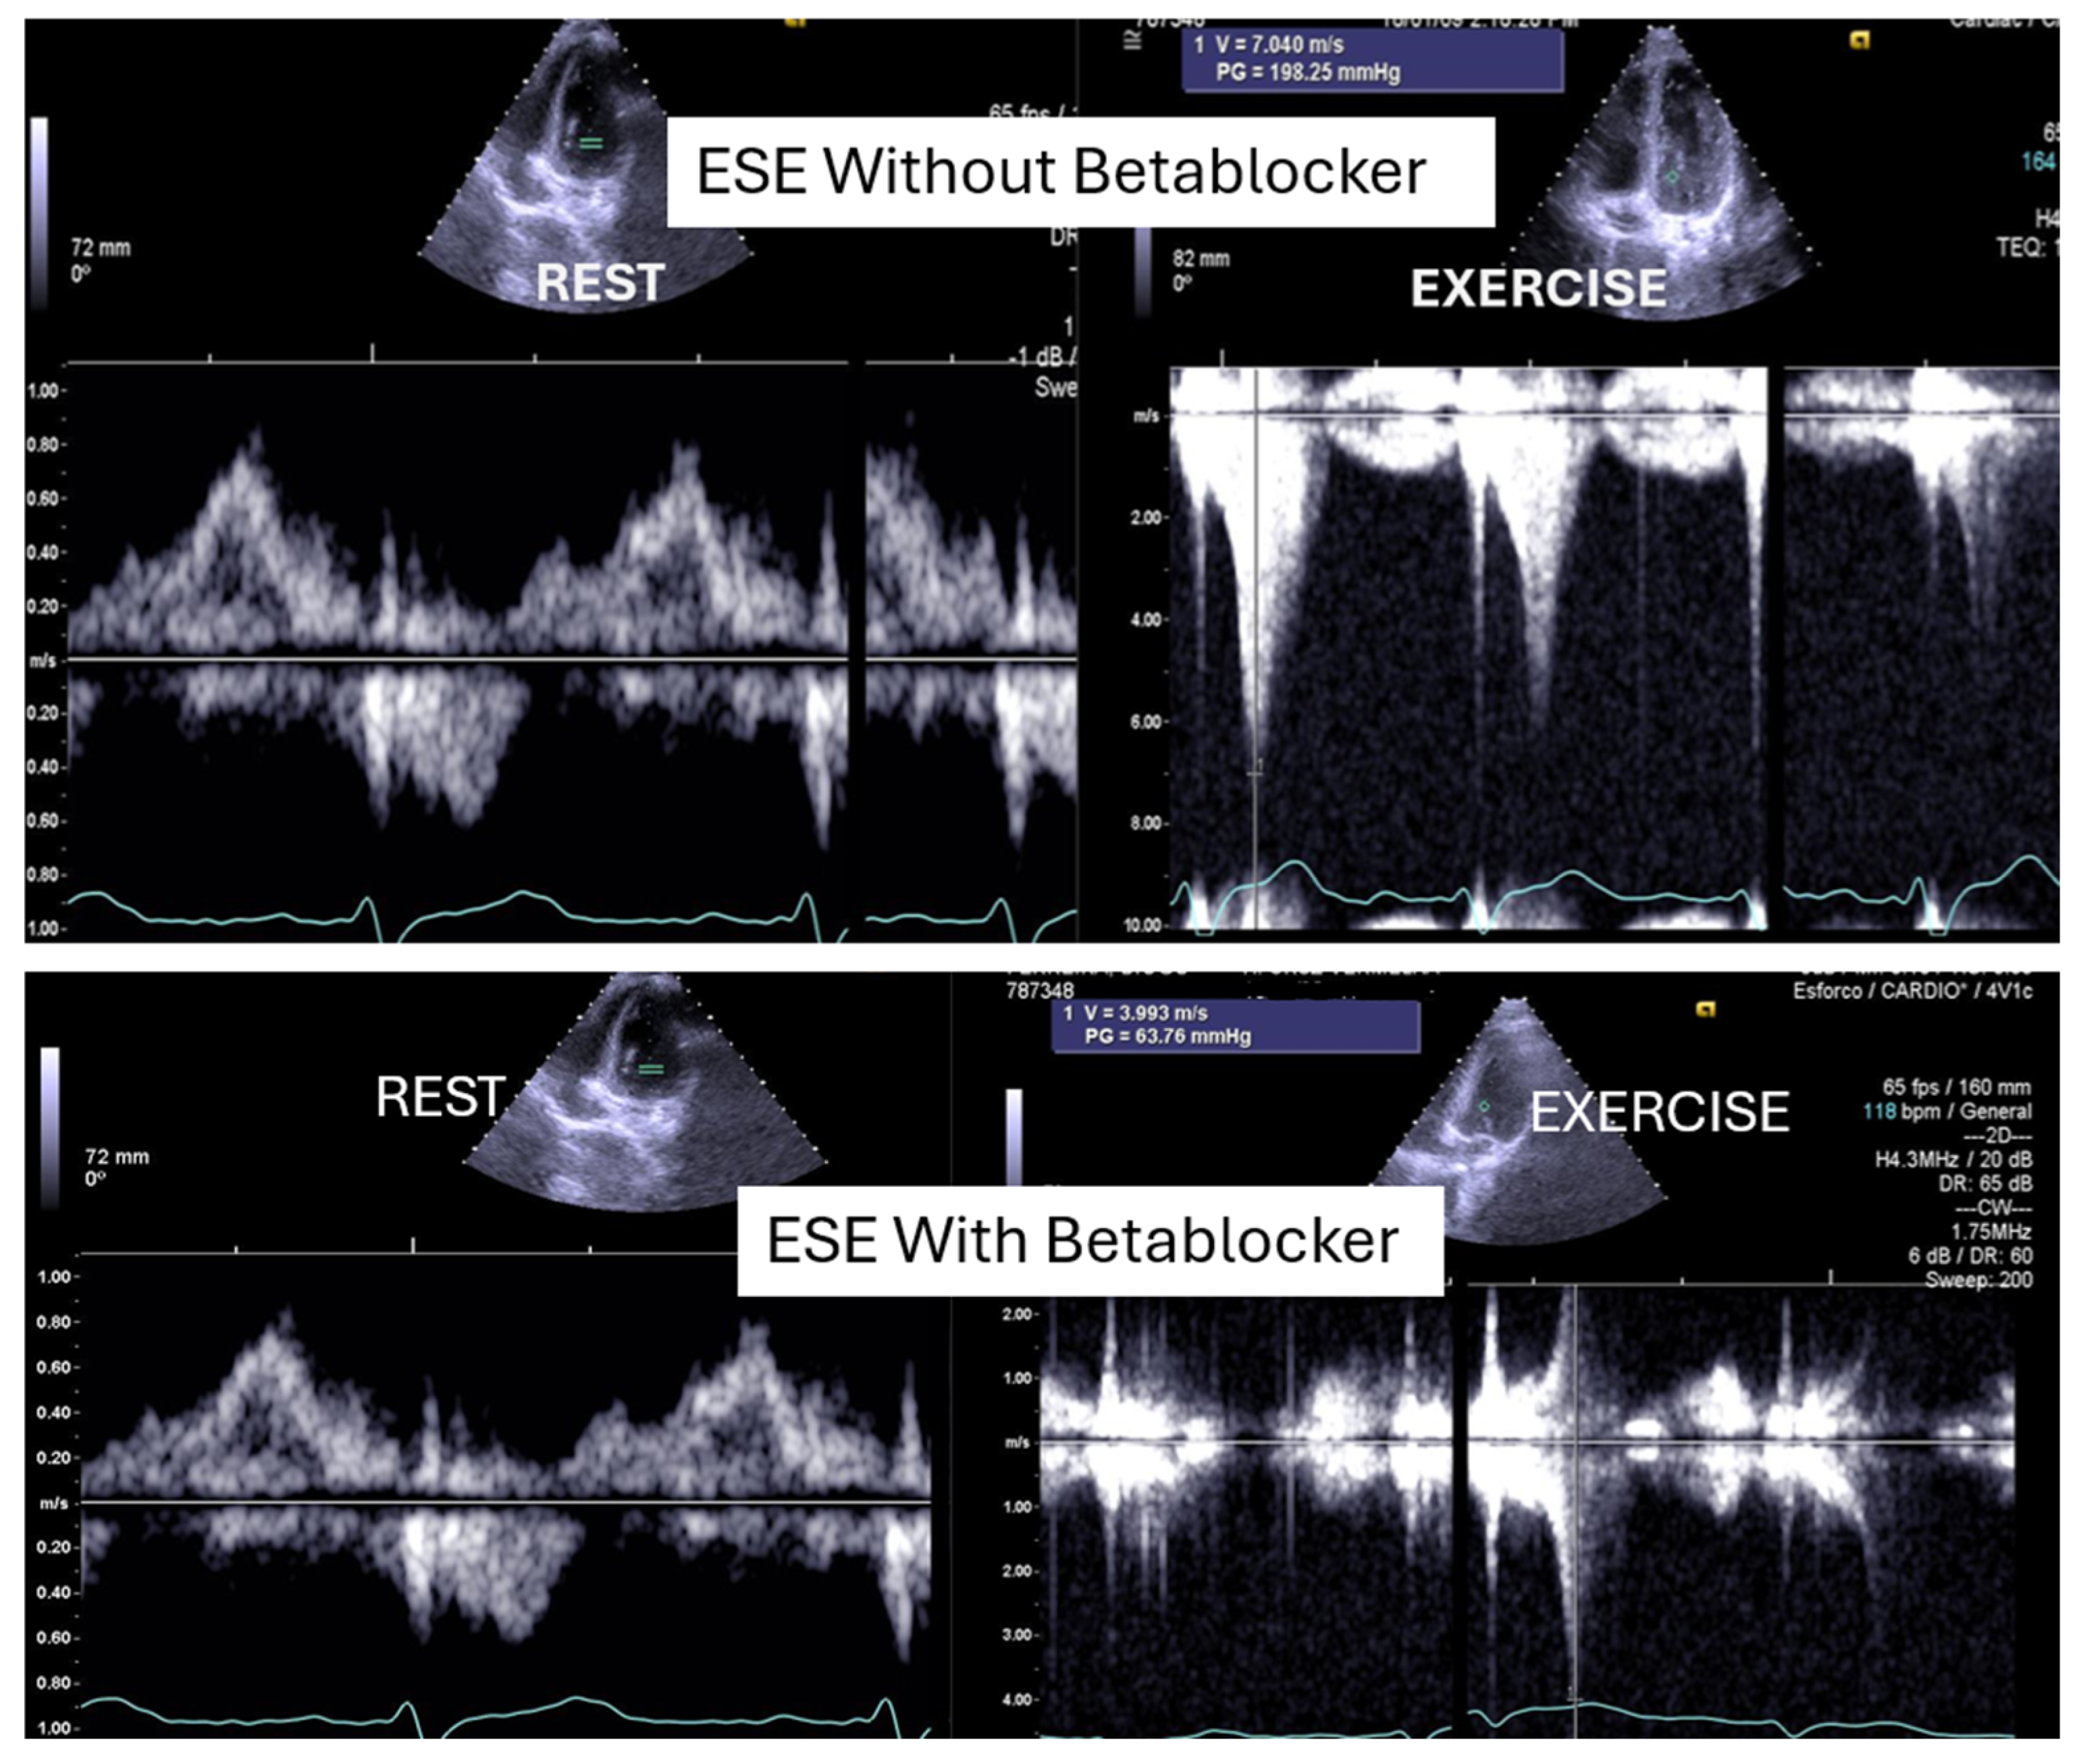

Figure 2.

This figure depicts an intraventricular pressure gradient observed during exercise in an adolescent presenting severe exertional dyspnea, accompanied by pronounced systolic anterior motion (SAM) of the mitral valve.

On the resting echocardiogram, all the exams were considered normal with and without beta-blockers. No wall motion abnormalities were detected in any of the exams, with or without beta-blockers. In the complete group, IVPG (Figure 1) at peak exercise on the first assessment was 105 ± 38 mmHg, with mitral valve SAM in 28 adolescents (Figure 2). Among the 29 adolescents treated with beta-blockers, IVPG was 58 ± 32 mmHg, p < 0.0001.

One of these adolescents also developed “lung comets” [21,22,23,24,25]. These were investigated due to severe dyspnea associated with marked systolic anterior motion (SAM) and a significant intraventricular pressure gradient (IVPG) (Figure 3). To the best of our knowledge, this is the first report describing the presence of lung comets during exercise stress echocardiography (ESE) in pediatric patients, specifically in association with severe exercise-induced IVPG.

According to the 2021 universal definition of heart failure by the European Society of Cardiology, diagnosis is based on the presence of typical signs and symptoms, corroborated by elevated natriuretic peptide levels and/or objective evidence of cardiogenic pulmonary or systemic congestion [24]. In the present case, following a stepwise titration of beta-blocker therapy—from bisoprolol 2.5 mg, 5 mg, 7.5 mg, and 10 mg to atenolol 50 mg—the adolescent no longer exhibited lung comets (Figure 4).

In our study, beta-blocker therapy was associated with reductions in heart rate, exercise-induced ST-segment alterations, systolic blood pressure, and, consequently, peak heart rate–systolic blood pressure product (HR × SBP). The incidence of intraventricular gradients (IVGs) (Figure 1) and systolic anterior motion (SAM) of the mitral valve (Figure 2) during exertion also decreased significantly. These hemodynamic improvements were accompanied by a notable reduction in symptoms during exercise testing and follow-up

The condition was managed using bisoprolol, which led to clinical improvements and substantial reductions in intraventricular pressure gradients (IVPGs). It has long been recognized that small intraventricular pressure gradients are a common phenomenon. Three mechanisms have been proposed to explain their significant increase during exercise: (1) an amplification of non-obstructive physiological gradients, (2) end-systolic obstruction due to mid-cavity obliteration of the ventricle, and (3) mid-systolic obstruction caused by systolic anterior motion (SAM) of the mitral valve, which restricts blood ejection [2,3].